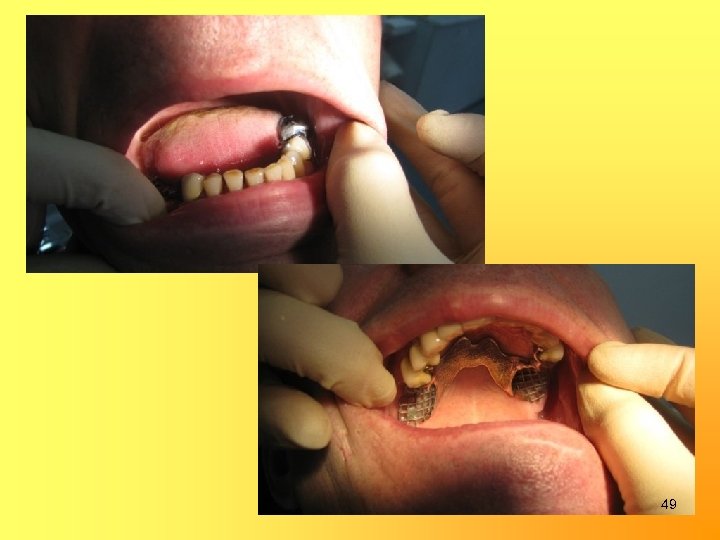

Изготовление бюгельных протезов в/ч и н/ч с замковыми креплениями на 15, 24, 43 и опорно-удерживающими кламмерами на 37 и 35 35

48

49